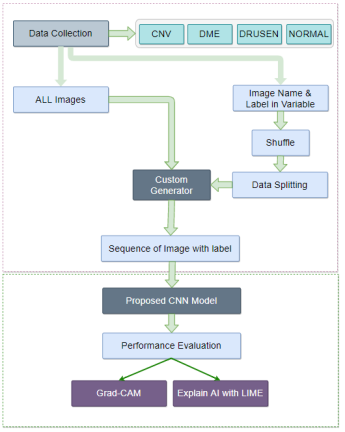

III-A Proposed Retinal OCT Model

Our dataset, containing 84,495 X-ray images of four different categories including Normal, CNV, DME, DRUSEN [11]. For this huge dataset to proceed with the CNN model there is a resource-constrained. So, data is handled differently without preloading all images. Depending on the subfolders, each image is labeled accordingly. Labels and names of images are stored in two different variables. They are partitioned into two different disjoint sets as train and test after shuffling. A custom image generator works in the middle to produce a batch of image files using labels and names. The batch size can easily be manipulated based on available resources. These batches of images are sequentially fed into a custom-made 6-layer CNN model. Testing data is employed to evaluate the performance. This model is then explained through LIME (Local Interpretable Model-agnostic Explanations), an explainable AI. This explanation can help to build trust among doctors to use CNN model as a solution in the medical field. However, it can also unveil hidden insight behind the model prediction.

III-B Data Acquisition and Preparation

Optical coherence tomography (OCT) images were selected from retrospective cohorts of adult patients from different hospitals around the world. OCT Images are labeled as (disease)-(randomized patient ID)-(image number by this patient) [11] and Fig 1 shows some examples of OCT images. Image properties are presented in Table II and the distribution of image quantity is presented in Table III. Custom image generators resize images to 224x224x3 and normalize them